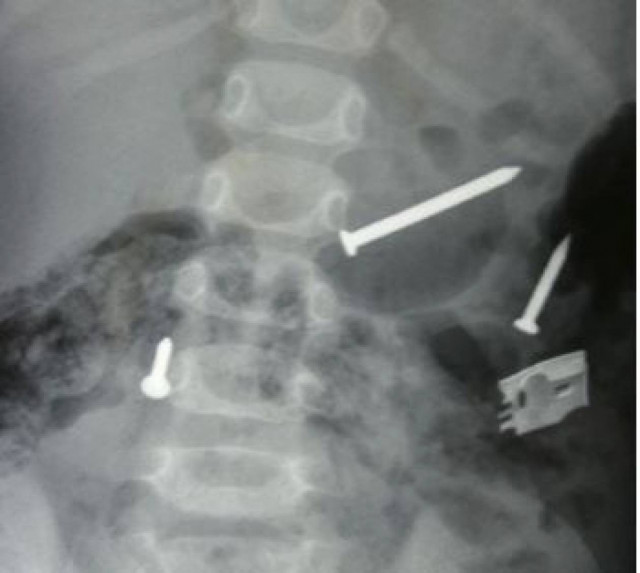

Δεν πίστευαν στα μάτια τους οι γιατροί στο Πανεπιστημιακό Νοσοκομείο του Ρίου, όταν είδαν τις ακτινογραφίες ενός ασθενούς από το ψυχιατρικό τμήμα, που είχε μεταφερθεί εκεί από την περιοχή του Μεσολογγίου.

Οι γιατροί είδαν στην ακτινογραφία να διαγράφονται, ένα ρολόι, κάποια δαχτυλίδια, κέρματα και βίδες. Επειδή τα αντικείμενα αυτά εγκυμονούσαν κινδύνους για την υγεία του ασθενούς, αποφασίστηκε να γίνει άμεσα επέμβαση ώστε να αφαιρεθούν.

Με τη βοήθεια της σύγχρονης τεχνολογίας κατάφεραν να απομακρύνουν από το «εσωτερικό» του ασθενούς, όλα αυτά που φαίνονταν στην ακτινογραφία. Σύμφωνα με πληροφορίες οι γιατροί συγκέντρωσαν περίπου 24 αντικείμενα...